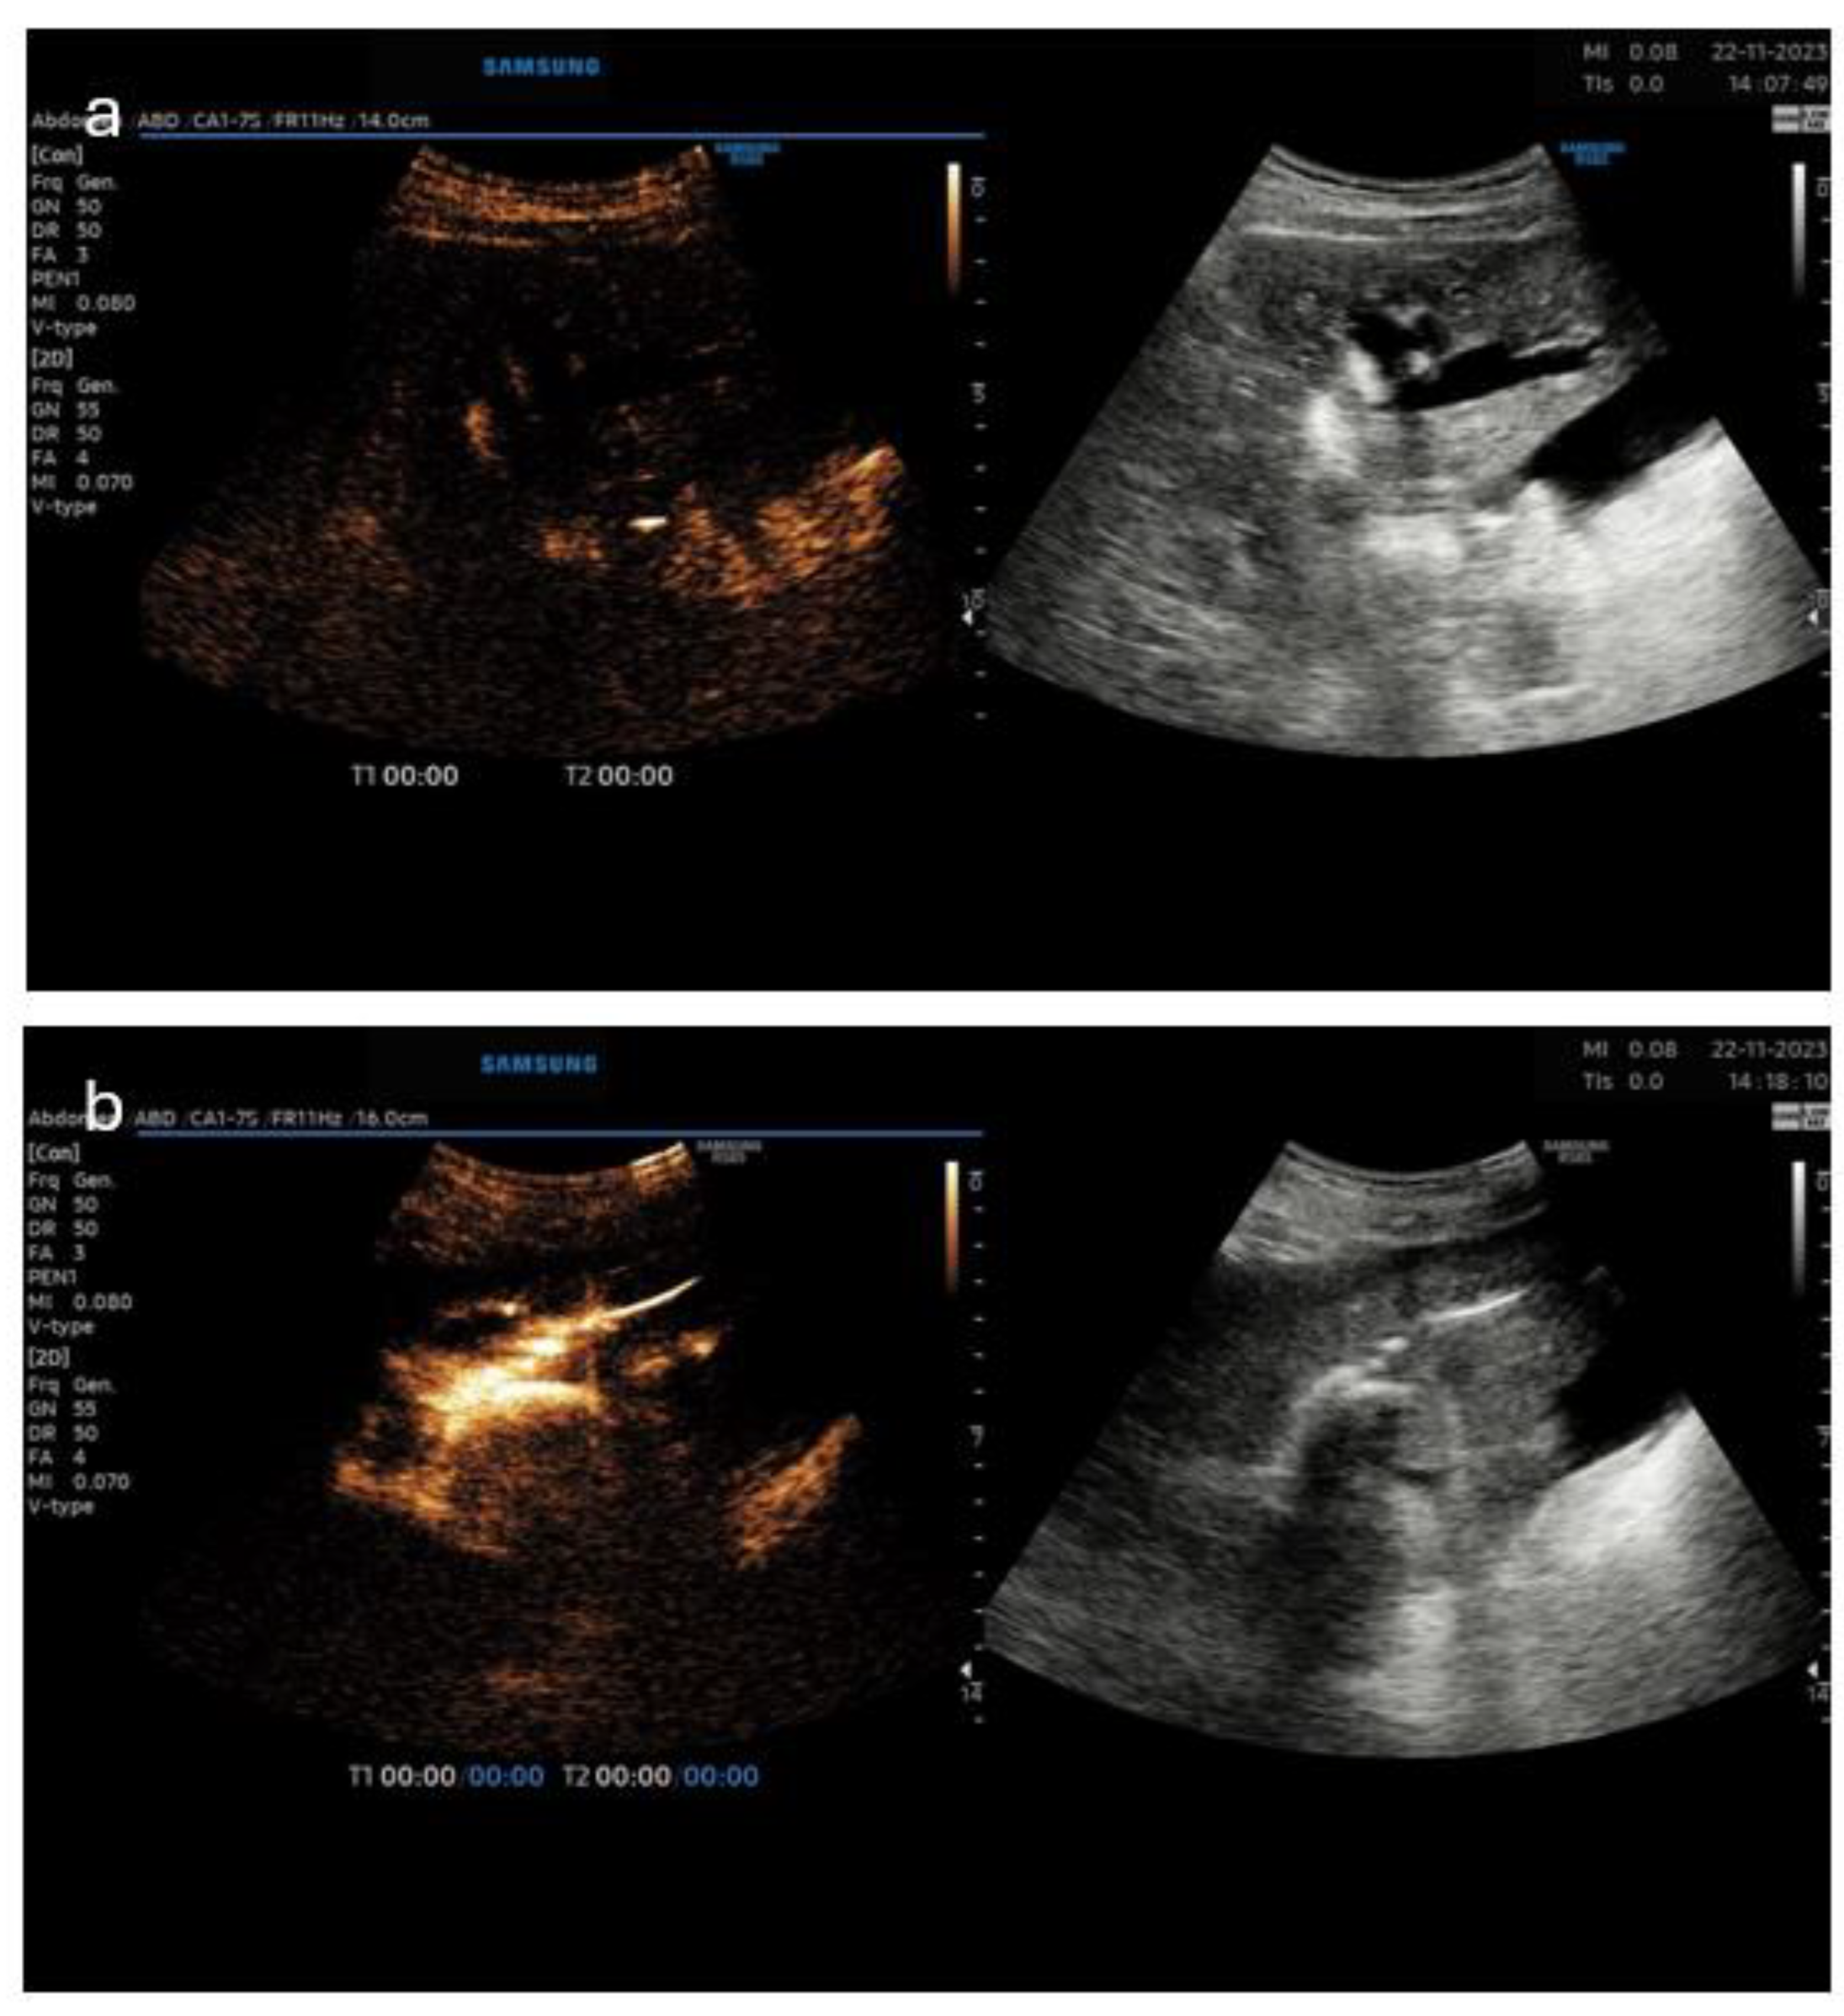

3.5. Pictorial Examples